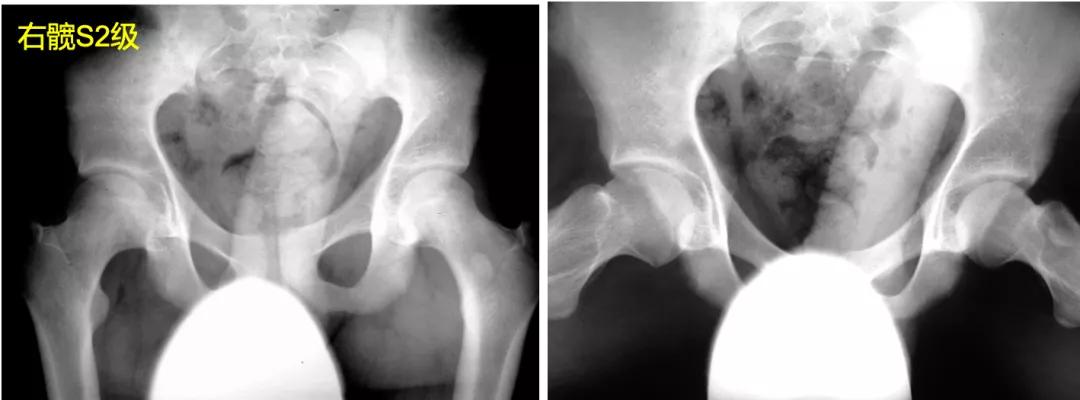

S3:股骨头呈卵圆形,在正位片或蛙式位片上,股骨头不圆>2mm。

S4:股骨头扁平,在正位片或蛙式位片上,股骨头负重区扁平>1cm,髋臼也呈扁平状,畸形匹配。